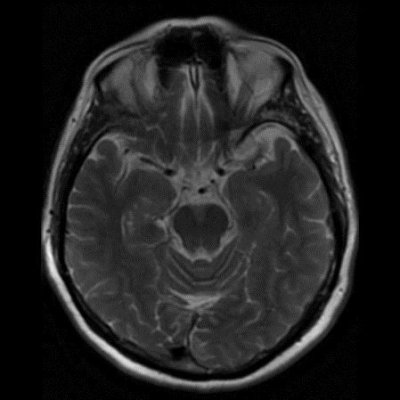

60 yaş, K

Baş ağrısı

Tanınız nedir?